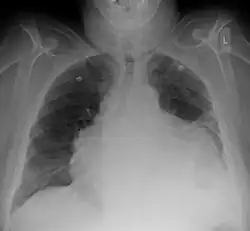

ECG: may present with sinus tachycardia, low voltage QRS as well as electrical alternans.[2] Due to the fluid accumulation around the heart, the heart is further away from the chest leads, which leads to the low voltage QRS. Electrical alternans signifies the up-and-down change of the QRS amplitude with every beat due to the heart swinging in the fluid (as displayed in the ultrasound image in the introduction) .[1] These three findings together should raise suspicion for impending hemodynamic instability associated with cardiac tamponade.

Echocardiogram (ultrasound): when pericardial effusion is suspected, echocardiography usually confirms the diagnosis and allows assessment of the size, location and signs of hemodynamic instability.[4] A transthoracic echocardiogram (TTE) is usually sufficient to evaluate pericardial effusion and it may also help distinguish pericardial effusion from pleural effusion and MI. Most pericardial effusions appear as an anechoic area (black or without an echo) between the visceral and the parietal membrane.[1] Complex or malignant effusions are more heterogeneous in appearance, meaning they may have variations in echo on ultrasound.[5] TTE can also differentiate pericardial effusion based on the size. Although it's difficult to define size classifications because they vary with institutions, most commonly they are as follows: small <10, moderate 10–20, large >20.[5] An echocardiogram is urgently needed for evaluation when there is concern for hemodynamic compromise, a rapidly developing effusion or history of recent cardiac surgery/procedures.[1]